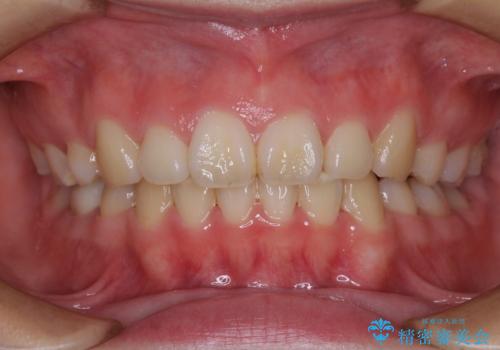

出っ歯による口の閉じにくさを治したい ワイヤー装置を用いた抜歯矯正

担当医 藤巻太一朗